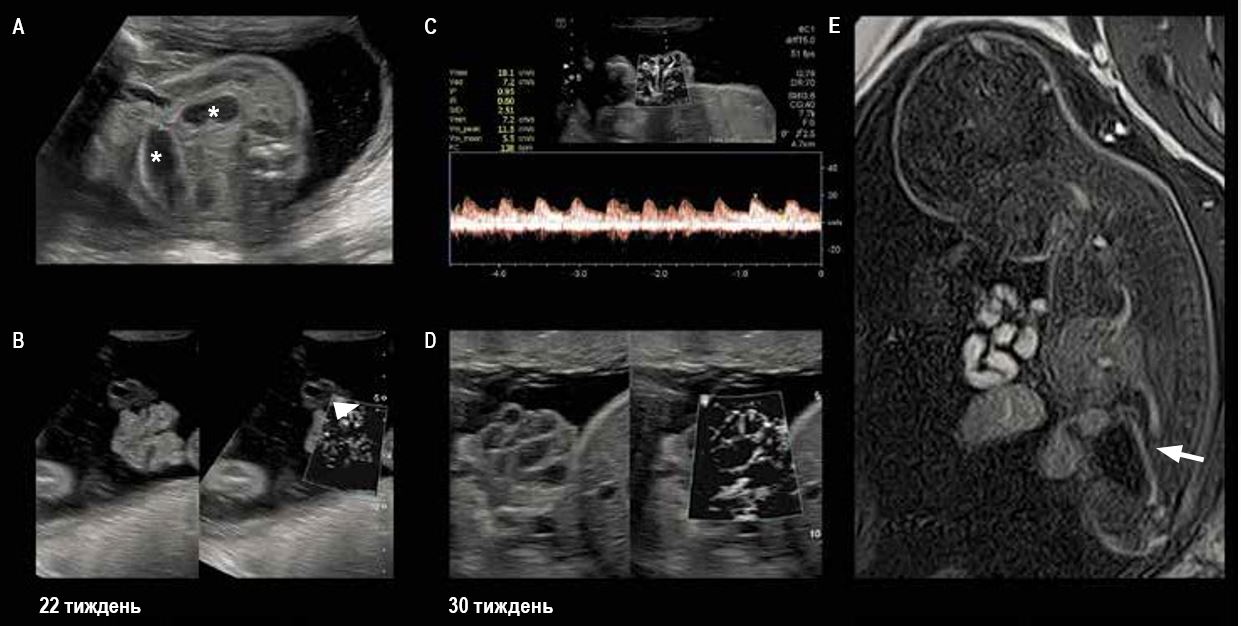

Мал. 2. ВЗРП із плацентарною ішемією.

Зверніть увагу на відсутність або зменшення щільності судинного компонента у плаценті при використанні технології SMI у різних досліджуваних областях.

Передчасні пологи на 28 тижні вагітності через прееклампсію. Маса тіла при народженні = 560 грам.

Гістологічне дослідження плаценти: великі зони маргінального інфаркту, пов'язані з дифузними ішемічними ураженнями

Хоріоангіома плаценти (мал. 3)

Хоріоангіома плаценти – це патологічне розростання кровоносних судин у субхоріонічній частині плаценти, що складається з численних дрібних капілярів у міксоїдній тканині. Великі хоріоангіоми можуть ускладнюватися водянкою плоду та внутрішньоутробною загибеллю плоду. Небезпека збільшується при екстенсивному кровопостачанні, оскільки це провокує розростання ураженої ділянки та приводить до ефекту «обкрадання». Навпаки, через значні некротичні зміни небезпека ускладнень зменшується. Моніторинг плода адаптований відповідно до цих умов.

Мал. 3. Гетерогенне ураження субхоріонічної плаценти поруч із місцем прикріплення входженням пуповини до плаценти:

A, B — при звичайному допплерівському картуванні видно лише найбільші артерії та вени;

C, D — ідентифікація кровотоку в мікросудинах у ураженій ділянці з використанням методу SMI підтверджує діагноз і уможливлює оцінку ризику гемодинамічної декомпенсації, а також виявлення зон із поганим кровопостачанням та некротичних зон.

Мал. 6. Гастрошизиз, діагностований при ультразвуковому дослідженні в першому триместрі; під час ультразвукового моніторингу на 22 тижні вагітності помічено обструктивний синдром:

A - дилатовані інтраабдомінальні кишкові петлі (зірочка), вузька шийка грижі розміром 6 мм;

B — плоскі петлі, що випали; той факт, що парієтальне кровопостачання добре проглядається за допомогою SMI, говорить про те, що петлі, що випали, мають нормальну життєздатність; диференціація від некротичних петель неможлива при використанні тільки В-режиму або енергетичного доплерівського картування;

C, D - це припущення підтверджено на 26-му, а потім на 30-му тижні вагітності при спостереженні за кровонаповненням стінок петель, що випали, і зовнішнього вигляду судин;

E - сагітальний зріз T1 при МРТ: вміст меконію в нормі при гіперінтенсивному сигналі петель, що випали; функціональний мікроколон (стрілка) нижче за закупорку